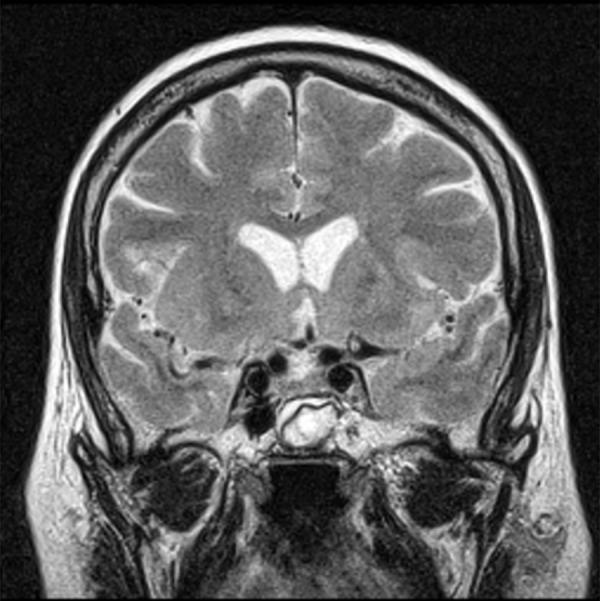

The proper diagnosis and management of patients after surgery for pituitary tumors are of great importance in clinical practice. The purpose of this study was to investigate the magnetic resonance features of the postoperative sella with fast spin echo T2-weighted imaging and to evaluate the benefits of this sequence compared to the classically performed contrast-enhanced T1-weighted imaging at 1.5T unit.

Contrast-enhanced T1-weighted imaging was significantly superior to T2-weighted imaging in assessment of infundibulum (p<0.05). There was no statistically significant difference for each of readers between T1- and T2-weighted images regarding to the following features: visualization of residual pituitary gland (p = 0.062 and p = 0.368), contours of pituitary (p = 0.959 and p = 0.265), optic chiasm (p = 0.294 and p = 0.843), and visualization of presence of residual tumor (p = 0.204 and p = 0.169). T2-weighted images were significantly superior to contrast-enhanced T1-weighted imaging with regard to visualization of contours of residual tumors (p<0.05).

CONCLUSIONS

T2-weighted images may help to discriminate tumorous from non-tumorous involvement of the postoperative sella and the sphenoid sinus. T2-weighted images are also very useful for a long time after the resection in the postoperative evaluation of the implanted muscle with fascia.

在临床实践中,对垂体瘤术后患者的正确诊断和管理非常重要。本研究的目的是探讨快速自旋回波 T2 加权成像在术后鞍区的磁共振特征,并评估该序列与 1.5T 单位常规进行的增强 T1 加权成像相比的优势。

增强 T1 加权成像在评估漏斗方面明显优于 T2 加权成像(p<0.05)。对于每个读者来说,T1 加权和 T2 加权图像在以下特征方面的表现没有统计学差异:残留垂体的可视化(p=0.062 和 p=0.368)、垂体轮廓(p=0.959 和 p=0.265)、视交叉(p=0.294 和 p=0.843)和残留肿瘤的可视化(p=0.204 和 p=0.169)。T2 加权成像在显示残余肿瘤的轮廓方面明显优于增强 T1 加权成像(p<0.05)。

结论

T2 加权图像可能有助于区分术后鞍区和蝶窦中肿瘤性和非肿瘤性病变。T2 加权图像在切除术后植入的肌肉和筋膜的长期随访中也非常有用。